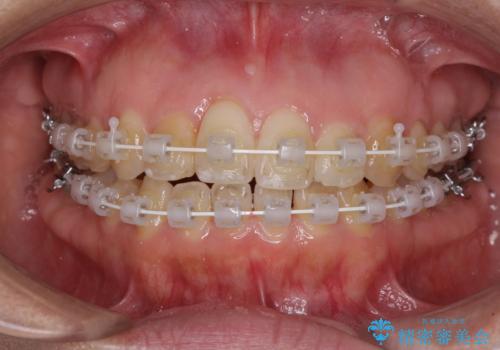

治療開始後すぐに妊娠され、つわりと闘いながらの矯正治療となりました。

上下顎でゴムかけを行ったのですが、早く終わらすためにしっかりと装着していただき、無事出産前に装置を外すことができました。